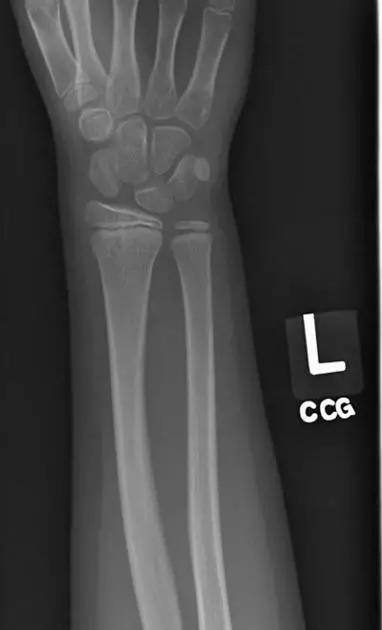

2. Colles 骨折

桡骨远端骨折,伴有桡骨远端向背侧的移位,可以有或没有尺骨干的骨折。具有这几个特征:背侧粉碎、向背侧成角、向背侧移位且挠骨短缩的关节外骨折。

典型 colles 骨折,枪刺样、餐叉样畸形

3. Smith 骨折

桡骨远端骨折伴骨折远端向掌侧移位,也称为反 Colles 骨折。

来源:radiology assistant